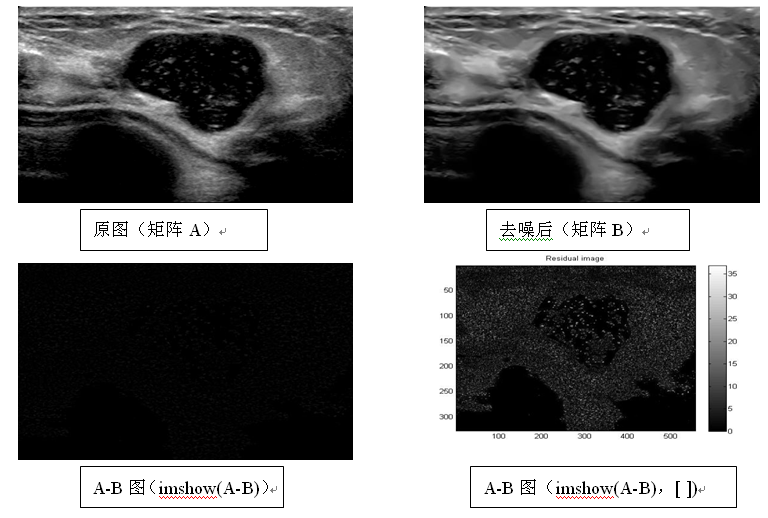

"去噪"前后的两幅图,"减法处理"的效果为什么和文献不一样?